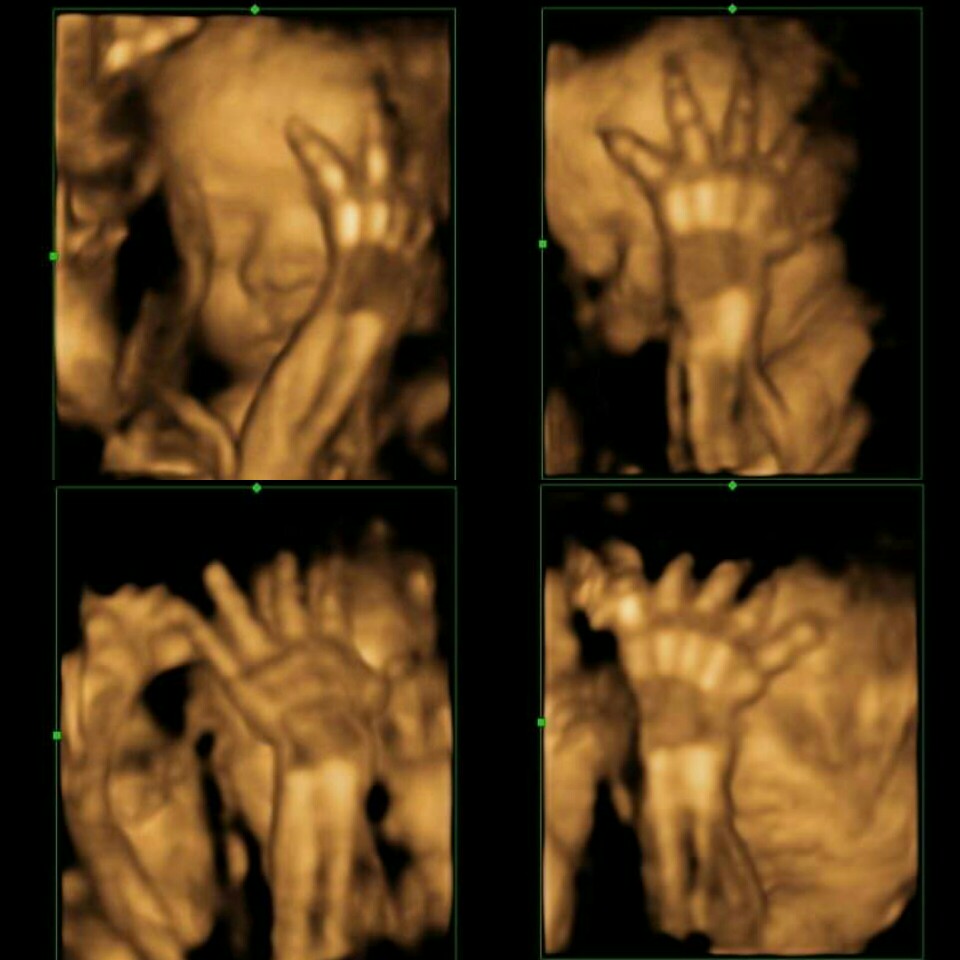

บ้านนี้ชอบเอาเท้าบัง มือบังค่ะ

บ้านนี้เอามือปิดแบบนี้เลยจ้า555

บ้านนี้ ยกขาสูงไปหน่อยจ้า 555